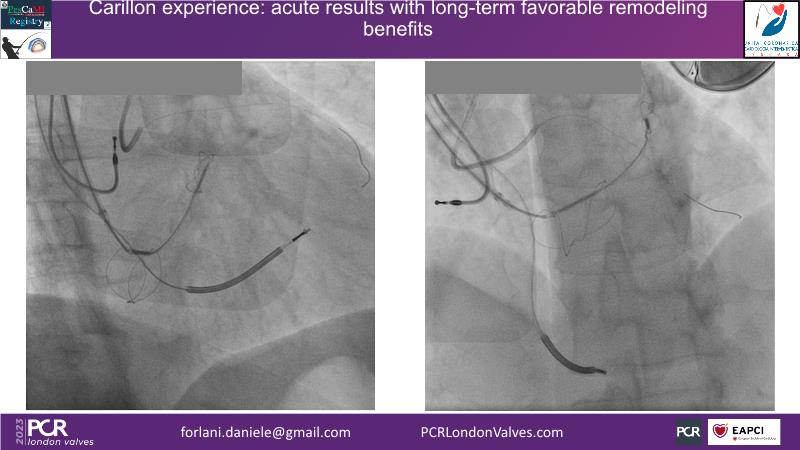

This session offers insights into combo therapy involving Carillon for patients with functional mitral regurgitation. It covers details of the EMPOWER trial, a double-blinded, sham-controlled study, and explores the potential benefits of early treatment for patients with functional mitral regurgitation.